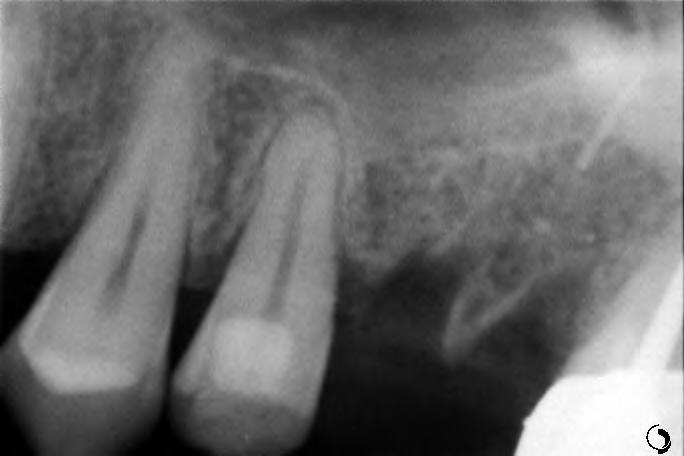

Greffe osseuse: Dans certains cas, la quantité d’os disponible dans la mâchoire n’est pas suffisante pour poser un implant de manière stable et durable. Pour recréer un volume adapté, différentes chirurgies pré-implantaires peuvent être proposées :

La greffe d’apposition (horizontale ou verticale) : cette technique consiste à ajouter de l’os pour élargir ou rehausser la mâchoire. Elle permet d’obtenir une base osseuse solide et adaptée à la pose de l’implant.

Greffes de tissus mous: il s’agit d’épaissir ou d’augmenter la gencive autour de la future zone implantaire. L’objectif peut être esthétique (améliorer l’apparence “gingivale”), améliorer la santé des tissus mous, protéger l’implant, et assurer une barrière biologique efficace.